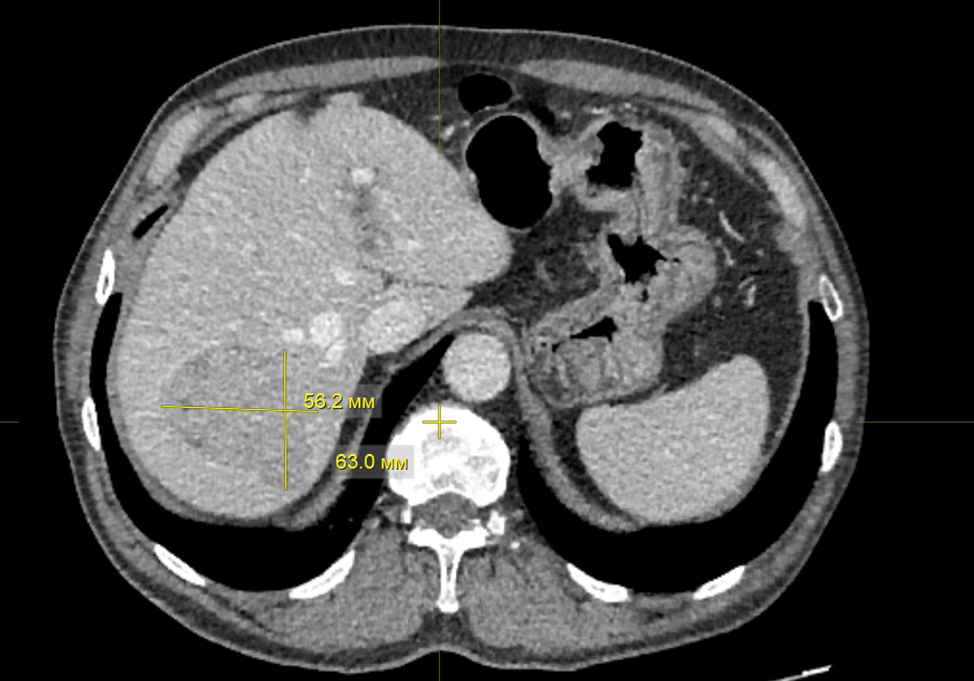

Описание клинического случая. В статье описан случай струмального карциноида яичника гигантских размеров с отдаленным метастазом в полость правого предсердия в виде флотирующего тромба и его радикального хирургического лечения, проведенного в два этапа.

Заключение. Данный клинический случай демонстрирует важность всесторонней предоперационной диагностики, интраоперационной оценки и гистопатологического диагноза. При данной патологии, протекающей чаще бессимптомно, различные диагностические обследования имеют низкую специфичность и чувствительность, и в большинстве случаев диагноз устанавливается на основании результатов послеоперационного патологоанатомического исследования.